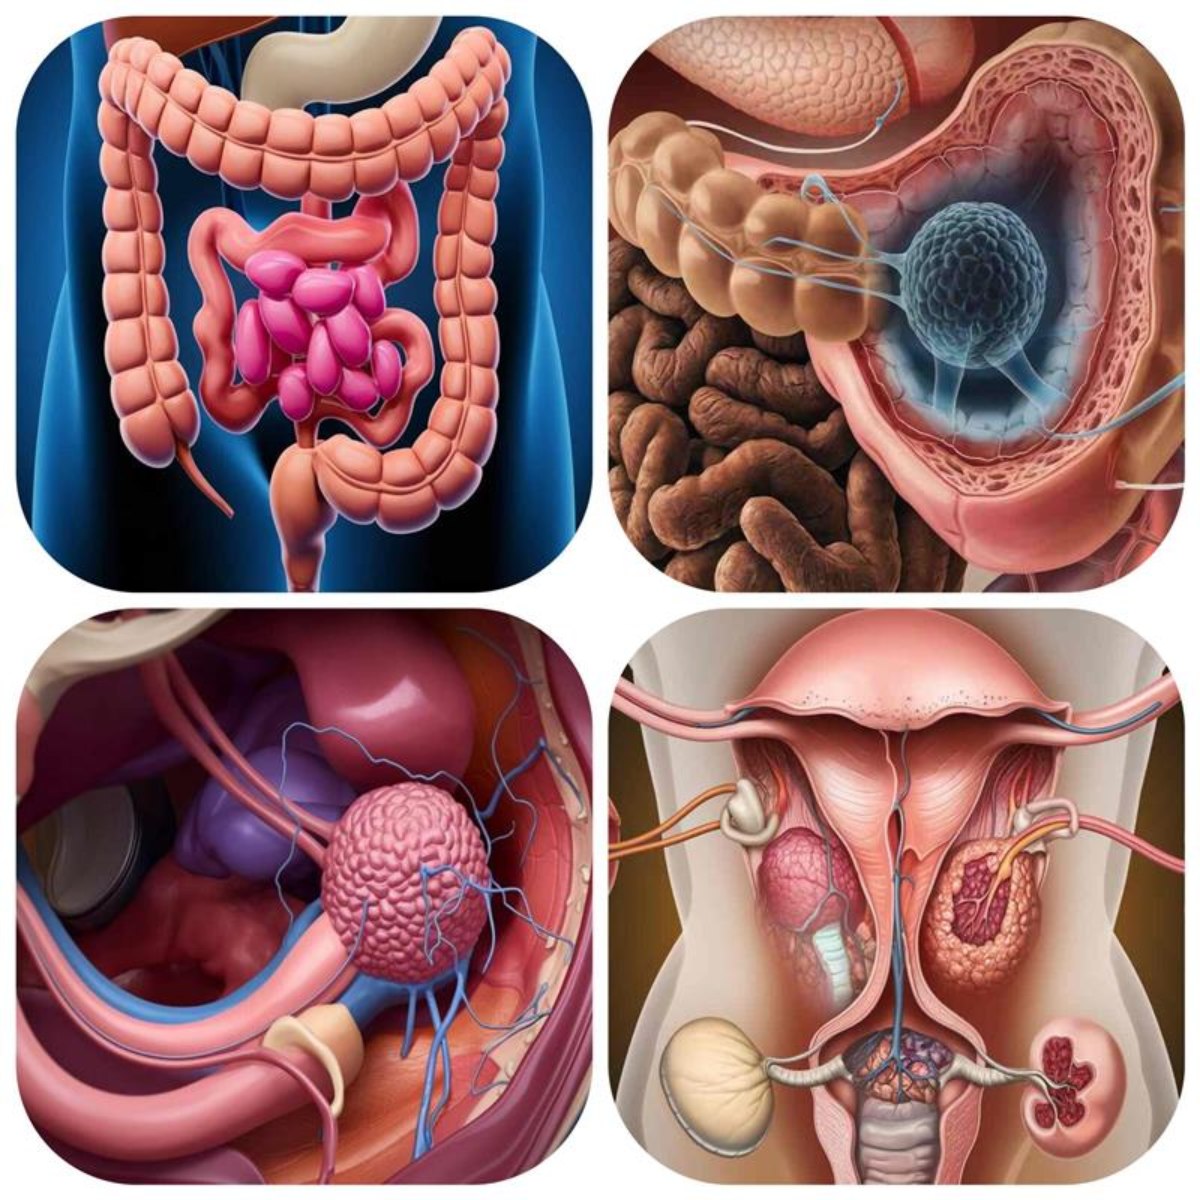

Cancers Commonly Associated With Bowel Leakage

Cancers commonly associated with bowel leakage include colorectal, rectal, and anal cancers, as these directly affect the digestive tract and bowel control. In some cases, gynecological cancers such as cervical or ovarian cancer can also contribute to leakage by spreading to nearby tissues and nerves.

| Colorectal Cancer | Tumors in colon/rectum disrupt bowel control |

| Rectal Cancer | Damages rectal nerves and sphincter muscles |

| Anal Cancer | Affects anal sphincter, leading to leakage |

| Gynecological Cancers | Pressure on rectum causes bowel dysfunction |

Colorectal Cancer

- One of the leading cancers associated with bowel leakage.

- Tumors in the colon or rectum can restrict the passage of stool and affect muscle control.

Rectal Cancer

- Affects the rectum, where stool is stored before elimination.

- Tumors may damage nerves and muscles directly responsible for continence.

Anal Cancer

- Involves the anal sphincter, a critical muscle for controlling bowel movements.

- Even small tumors can cause leakage.

Gynecological Cancers

- Ovarian and cervical cancers can press against the rectum.

- Women may experience leakage due to pelvic pressure and nerve disruption.